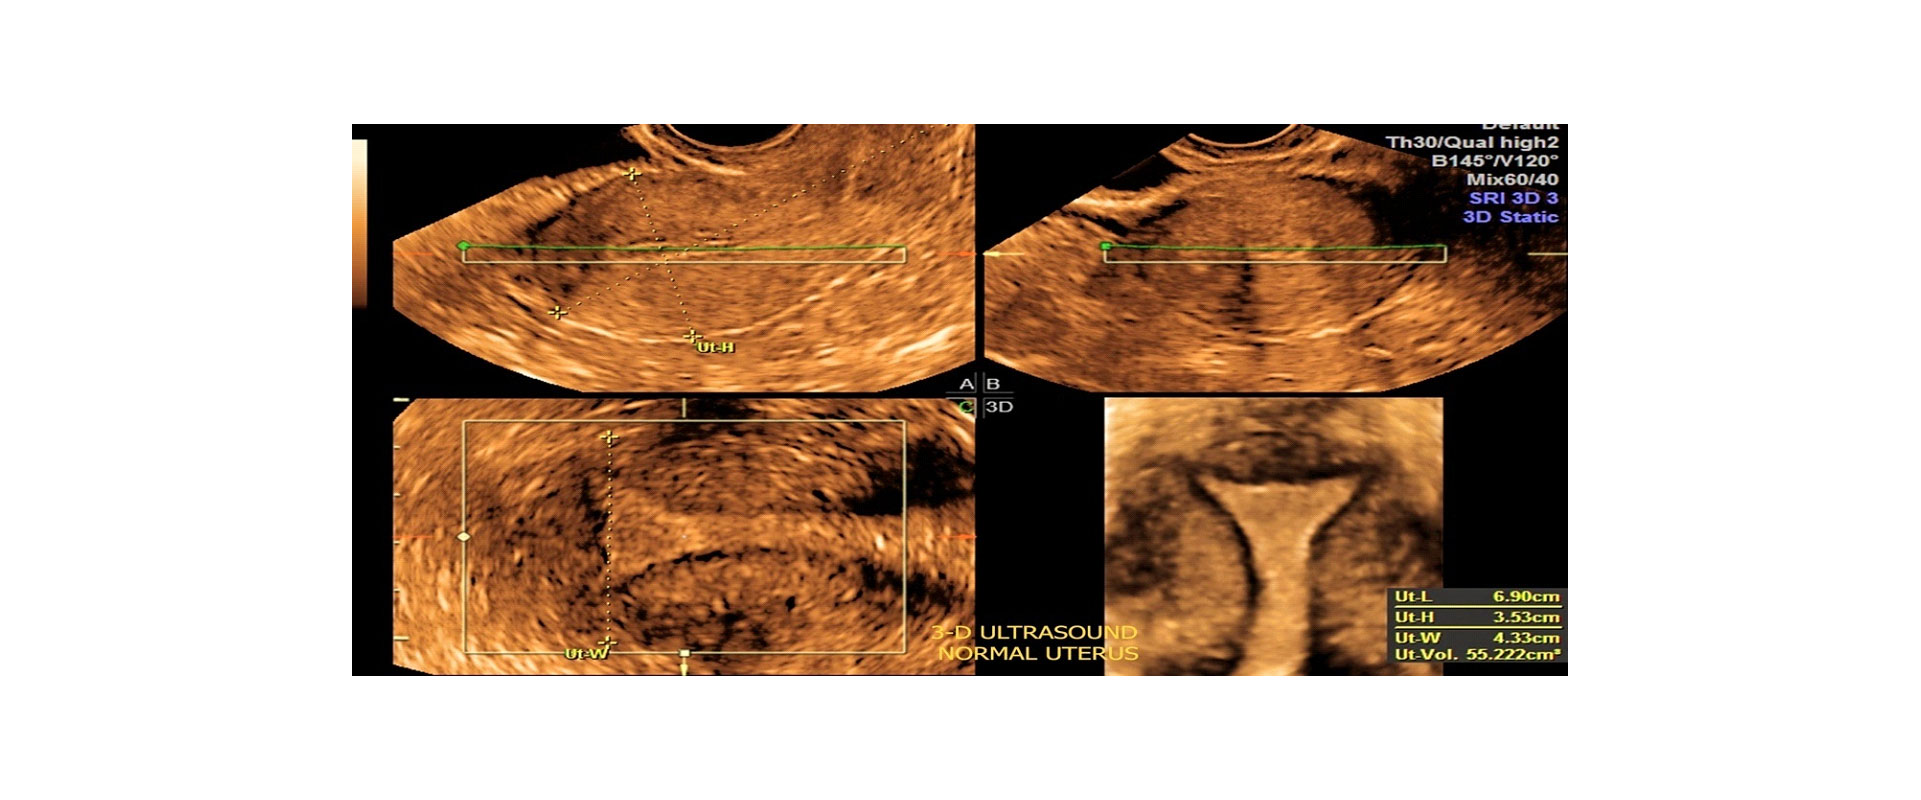

⦁ και τη φυσιολογική ανατομία της μήτρας και πιθανή παθολογία της

Στο ιατρείο μας χρησιμοποιούμε μηχάνημα υπερήχων τελευταίας τεχνολογίας έτσι ώστε να έχουμε ακίνητη τρισδιάστατη απεικόνιση του εμβρύου (3D) και της μήτρας ή να βλέπουμε το έμβρυο τρισδιάστατο όπως κινείται σε πραγματικό χρόνο – real time (4D).

✓Εκτίμηση Ανατομίας: Βελτιωμένη ανάλυση της ανατομίας των γυναικείων αναπαραγωγικών οργάνων.